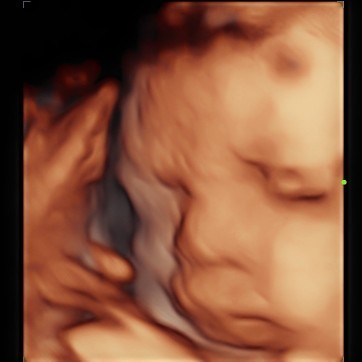

waktu 27 minggu, masyaAllah terlalu gemes🥰